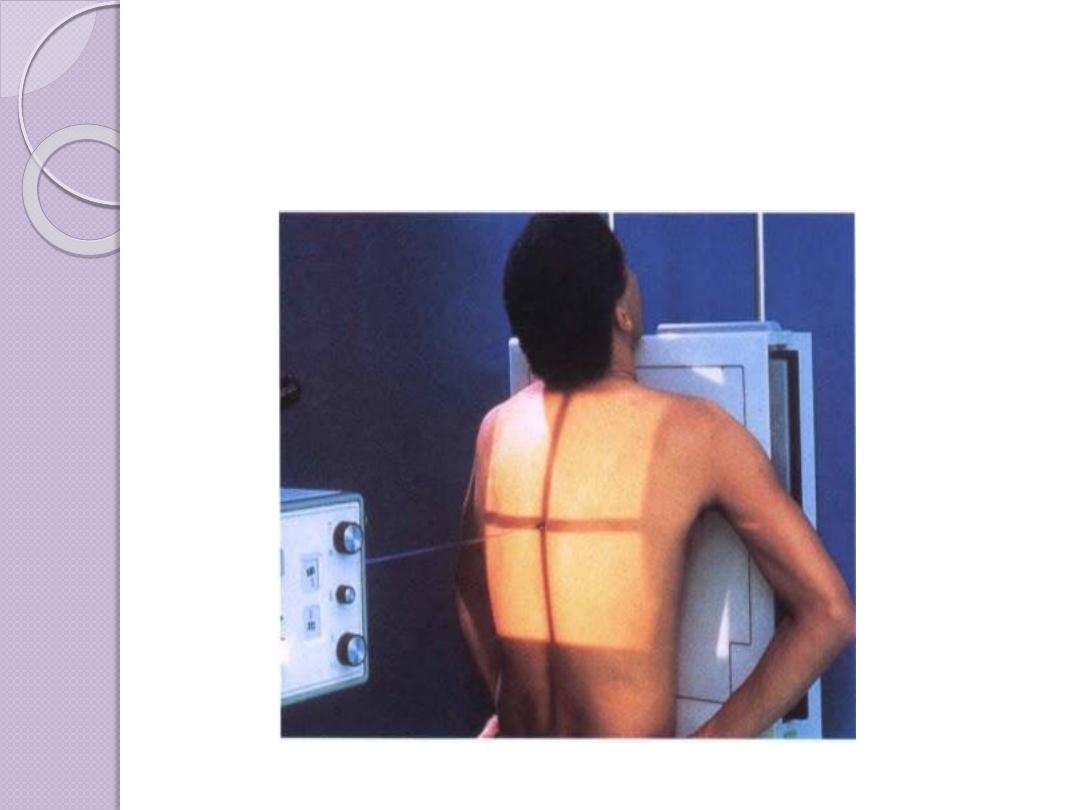

Radiographic Views

Chest and abdominal films are referred to as upright or

supine, depending on the position of the patient. In

addition, chest x-rays are usually described as

posteroanterior (PA) or anteroposterior (AP) or

lateral

These terms indicate the direction in which the x-ray

beam traversed the patient on its way to the detector.

PA means that the x-ray beam entered the posterior

aspect of the patient and exited anteriorly. AP means

that the beam direction through the patient was

anterior to posterior. A left lateral decubitus view is

one taken with the patient’s left side down.